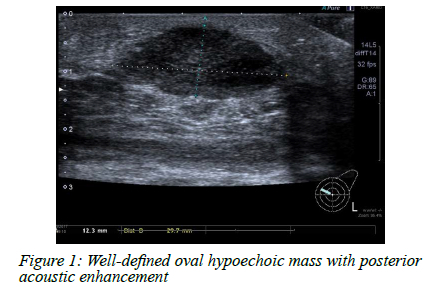

In nodular TB, an ultrasound scan often reveals a well-defined oval hypoechoic mass with posterior acoustic enhancement (Figure 1). The ultrasound picture may resemble a fibroadenoma. These hypoechoic lesions demonstrate no vascularity but rather a fluid collection containing debris. Ultrasound-guided aspiration of purulent fluid distinguishes these lesions from solid breast masses. In the sclerosing form, textural change with no visible fluid may mimic inflammatory carcinoma. The disseminated form of TB is associated with multiple anechoic collections, with and without debris, scattered throughout the breast with or without associated fistulation to the skin (Figure 2). Axillary lymphadenopathy is a common finding in breast TB; lymph nodes can show a spectrum of cortical thickening, solid or necrotic lymph nodes (Figure 3).2025